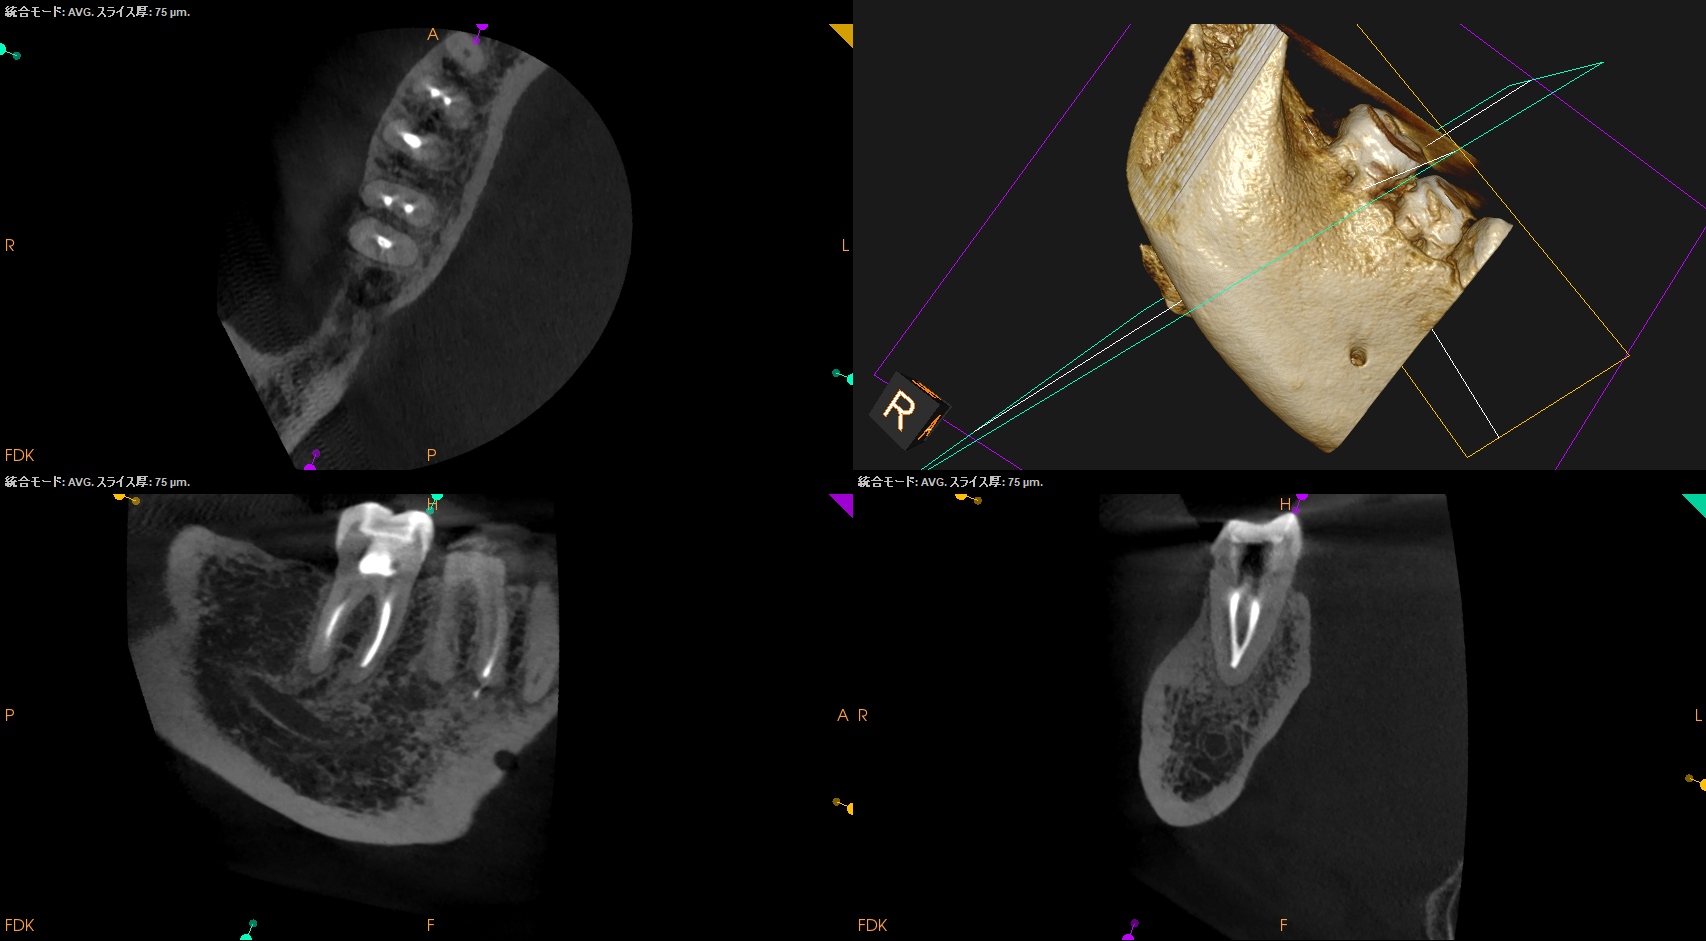

#31 RCT+Core build up(2025.9.12)

MLをメイン根管にし、MBがそこに合流する形式とした。

MLはMAFは当初は#40.04であったが#60.02に変更した。

炎症がまだ残存していると考え、MAFを#60.02まで上げた。

根充してPA, CBCTを撮影した。

MB

ML

D

問題はないだろう。